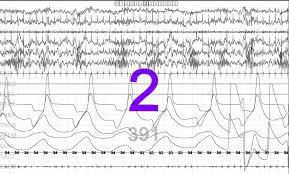

Epileptiform K Complexes And Sleep Spindles In Genetic Generalized Download Scientific Diagram

Stage N2 With K Complex And Sleep Spindles Download Scientific Diagram